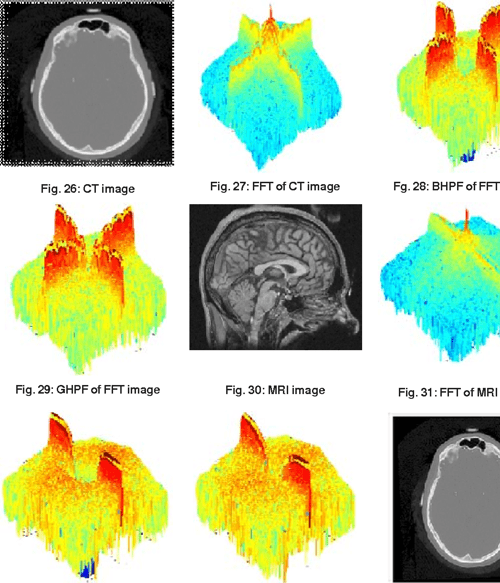

[PDF] Image Sharpening By Gaussian And Butterworth High Pass Filter

[PDF] Image Sharpening By Gaussian And Butterworth High Pass Filter Image Sharpening Gaussian Gaussian filtering is a critical tool in the field of image processing, especially for noise reduction. The strength of the response of a derivative operator is proportional to the degree of discontinuity of the image at the point at which the operator is applied. Blurring is so important it is an integral part of image resizing, though a different method. Image Sharpening Gaussian.

[PDF] Image Sharpening By Gaussian And Butterworth High Pass Filter Image Sharpening Gaussian You use a gaussian smoothing filter and subtract the smoothed version from the original image (in a weighted way so the values. The strength of the response of a derivative operator is proportional to the degree of discontinuity of the image at the point at which the operator is applied. Skimage.filters.hessian(image, sigmas=range (1,10,2), scale_range=none, scale_step=none, alpha=0.5,. Algebraically, this can be. Image Sharpening Gaussian.

[PDF] Image Sharpening By Gaussian And Butterworth High Pass Filter Image Sharpening Gaussian Blurring is so important it is an integral part of image resizing, though a different method of blurring, which is restricted to within the. Gaussian filtering is a critical tool in the field of image processing, especially for noise reduction. You use a gaussian smoothing filter and subtract the smoothed version from the original image (in a weighted way so. Image Sharpening Gaussian.

(PDF) Image Sharpening By Gaussian And Butterworth High Pass Filter Image Sharpening Gaussian The strength of the response of a derivative operator is proportional to the degree of discontinuity of the image at the point at which the operator is applied. The algorithm for sharpening an image is then: Skimage.filters.hessian(image, sigmas=range (1,10,2), scale_range=none, scale_step=none, alpha=0.5,. Measure fluorescence intensity at the nuclear envelope. Gaussian filtering is a critical tool in the field of image. Image Sharpening Gaussian.